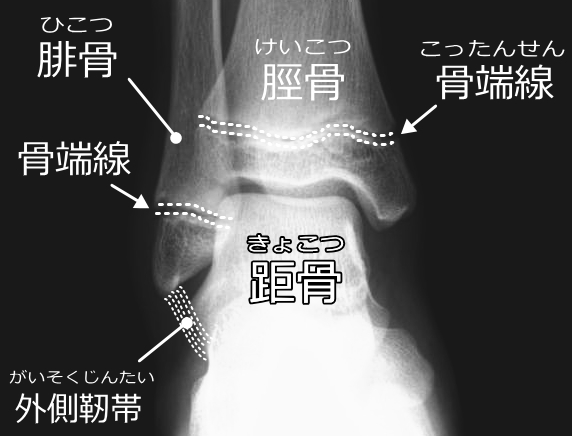

骨・骨端線・靱帯付着部(子どもならではの注意点)

成長期のお子さまの場合、靱帯より 骨・骨端線 (成長軟骨部) が弱いことがあり、以下のような損傷も併発しやすいです:

- 剥離骨折・骨端線離開:靱帯が付着している骨端部が強い力で引き剥がされる形で発生することがあります。

- 特に外くるぶし(腓骨遠位端)の骨端線・付着部に異常が出る可能性があります。

このような骨・骨端線の損傷を見逃すと、将来の成長や骨格バランスに影響を及ぼす恐れがあります。

剥離骨折・骨端線離開(骨の損傷)

- 成長期の子どもでは、靱帯より骨・骨端線(成長軟骨部)が弱いため、強い内反ストレスで「剥離骨折(付着部が剥がれる)」や「骨端線離開」が起きることがあります。

- これを見逃すと、将来的に成長異常・脚長差・変形を引き起こす可能性があります。

- したがって、「足首をひねったけど骨折ではない」と言われても、成長期なら骨端線まで確認できるかどうか検討が必要です。